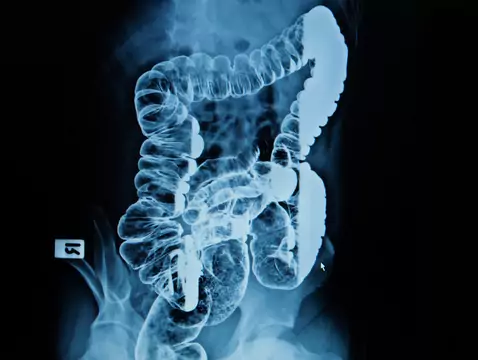

Intestinal angiodysplasia is categorised as a vascular malformation involving the intestines. Many patients present to a gastrointestinal specialist with strange, unpredictable bleeding involving the...